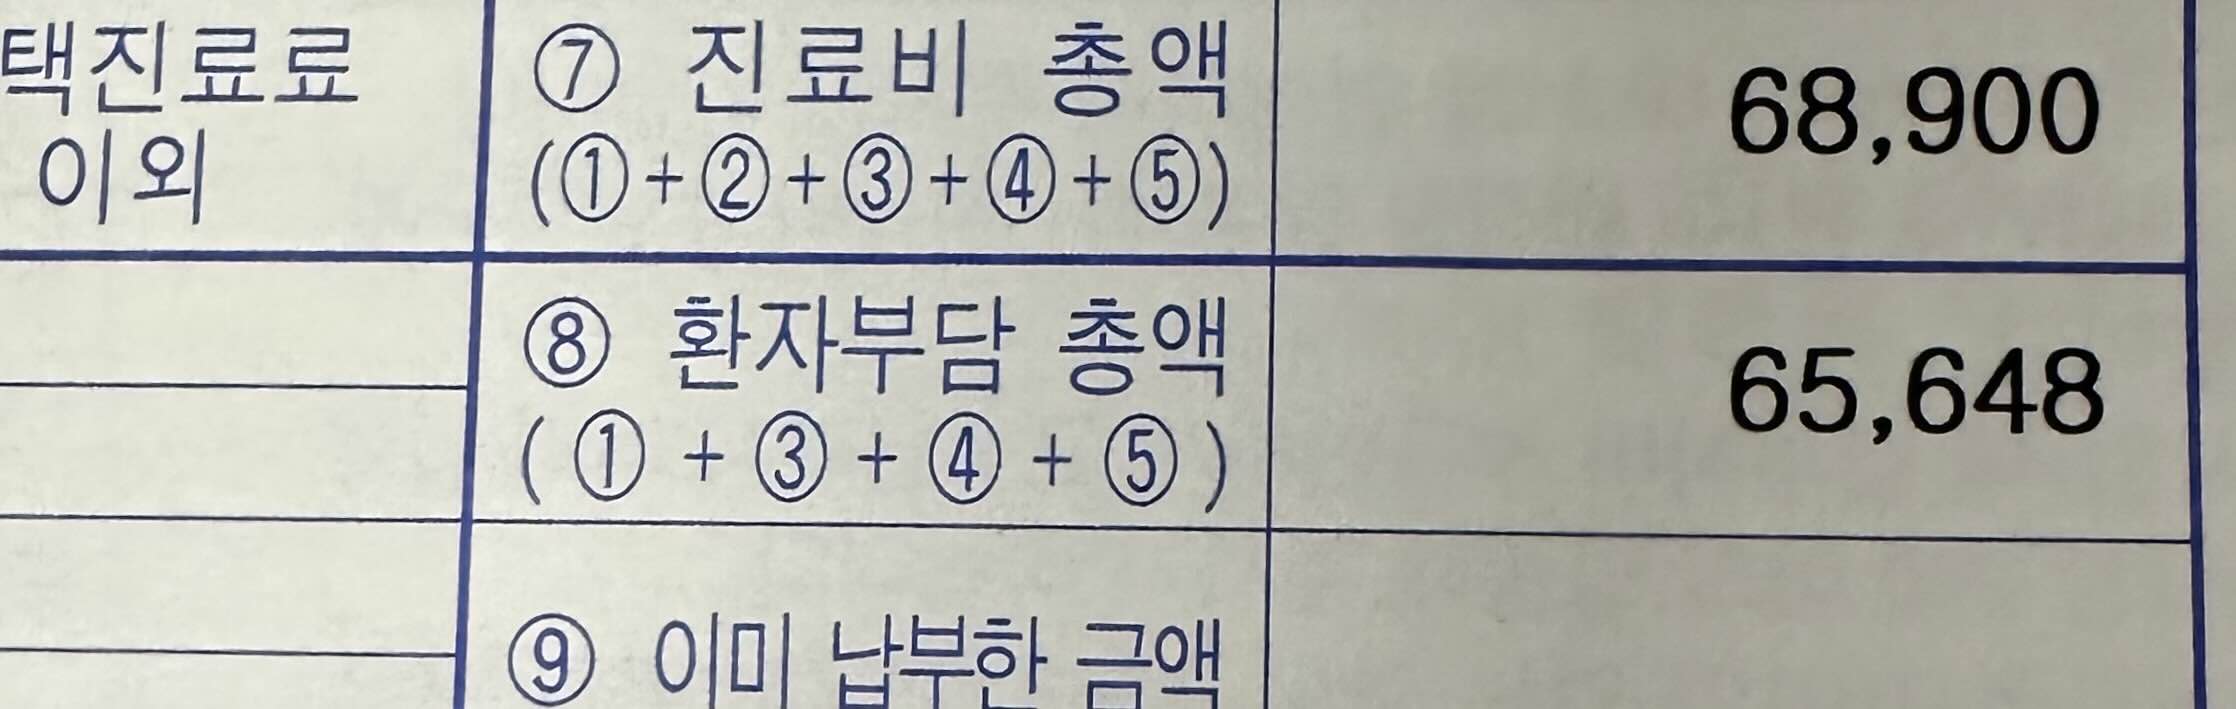

1. 외래 진료 후 청력검사와 고막의 개방증과 관련된 압력검사를 진행하였습니다. 진행비용은 병원마다 다르지만 대학병원에서의 검사 비용은 진료비 +검사비 40000원을 포함하여 저의 부담액은 65,648원 이었습니다. 검사를 진행하는 시간은 오래 걸리지 않았고 오히려 대기하는 시간이 더 걸렸던것 같아요.